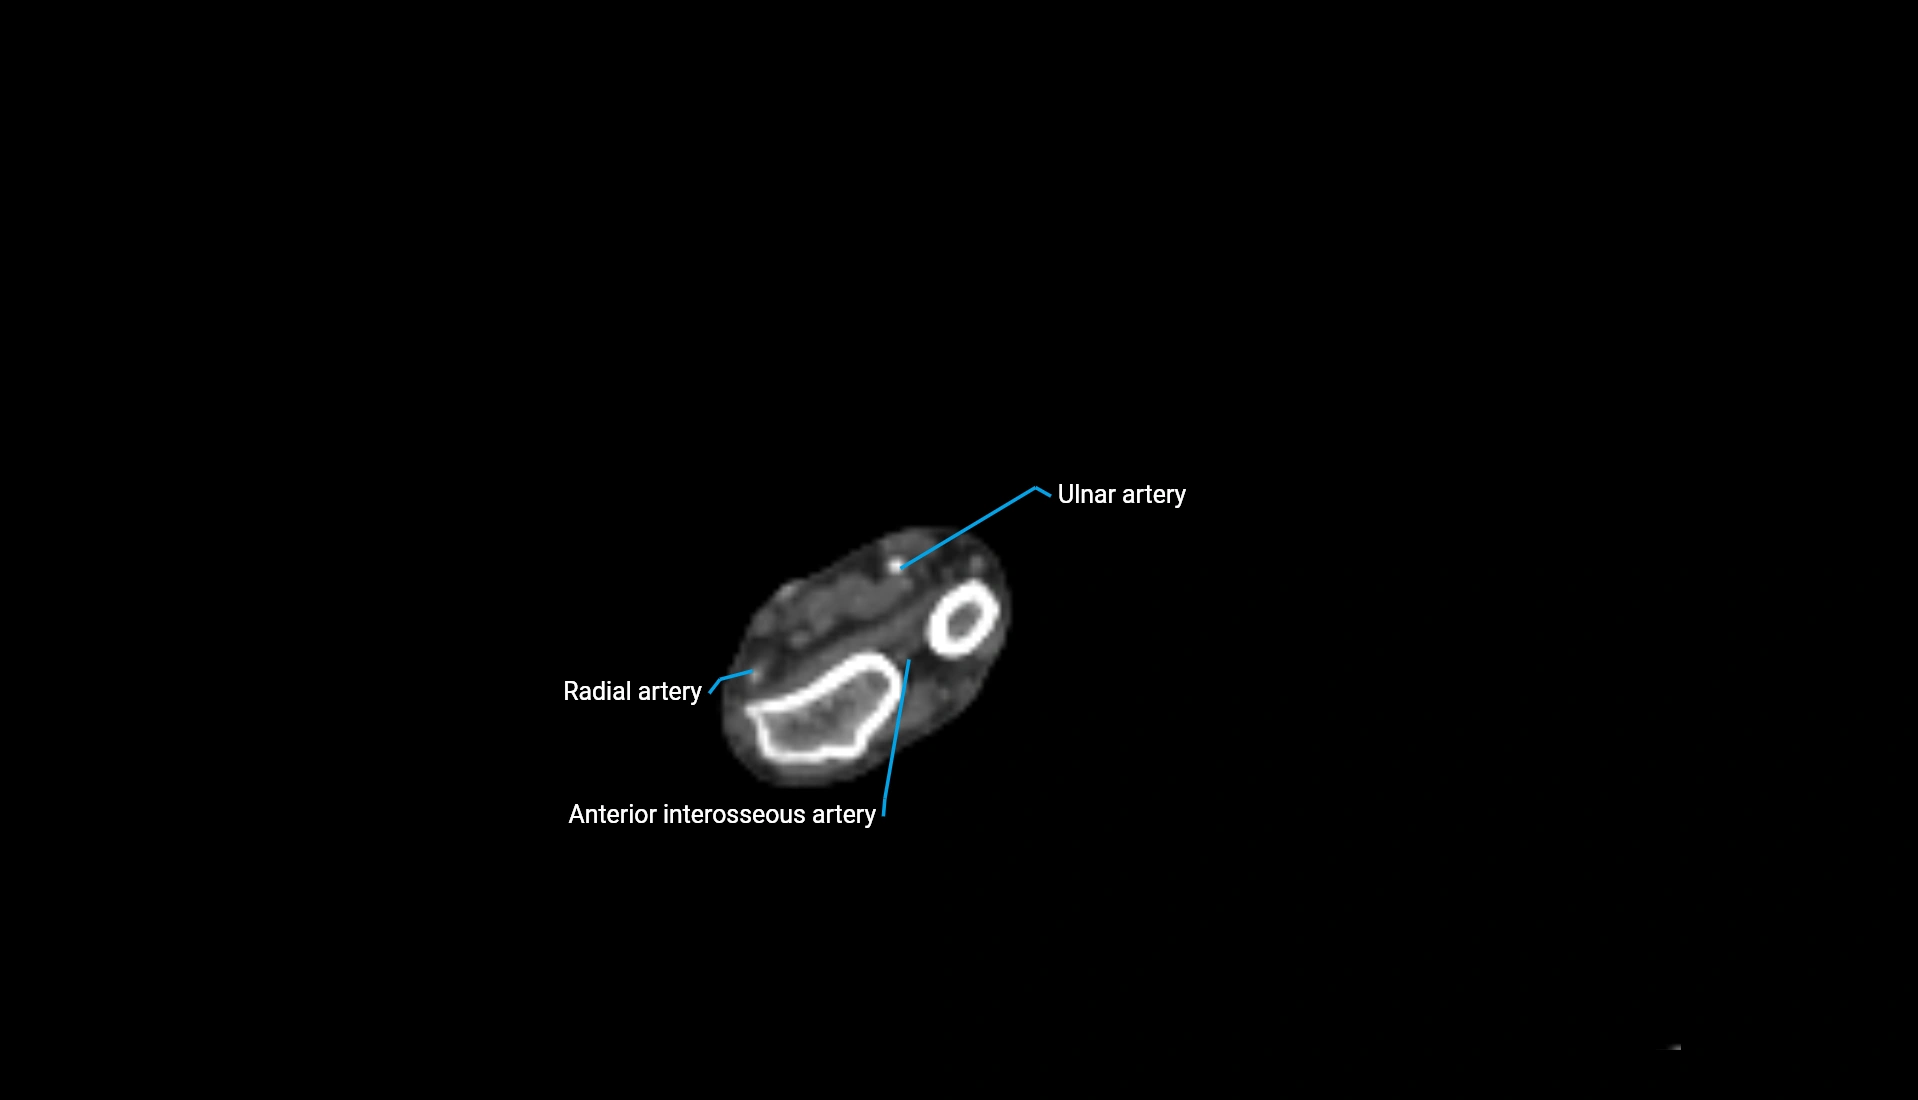

CT Appearance

Non-Contrast CT:

• Cortex: High-density, sharply defined

• Subchondral bone: Dense cancellous matrix

• Articular surface: Smooth concave contour articulating with the capitellum

• Excellent for evaluating bone integrity, alignment, and subtle fractures